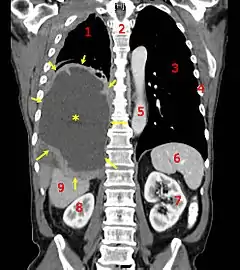

A coronal CT scan showing a malignant mesothelioma, indicated by the asterisk and the arrows | |